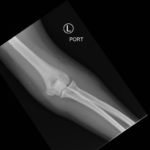

Posterior Elbow Dislocation

A 15-year old female presented with left elbow pain. While competing in a high school wrestling match, she extended her left arm to brace a fall and had immediate onset of sharp pain. She denied weakness or numbness of her left arm. She had no past medical history.

Elbow dislocations are classified by the position of the radio-ulnar joint relative to the humerus.1 Images 1, 2, and 3 show a left posterior elbow dislocation; the radius and ulna are displaced posteriorly with respect to the distal humerus. The lateral view of the elbow most clearly shows this: trochlear notch of the ulna is empty and displaced posteriorly relative to the trochlea. There is no associated fracture. Images 4 and 5 show the elbow status-post reduction, demonstrating proper alignment of the distal humerus with the radius and ulna.

Traumatic dislocations of the elbow are relatively uncommon in pediatric patients, with a peak incidence at 13 to 14 years.1 Dislocations are usually posterior and occur after forced abduction and extension of the elbow.1 It is important to evaluate for an associated fracture or avulsion, which occurs in over 50% of pediatric elbow dislocations. Fractures most commonly involve the medial epicondyle, radial head and neck, or coronoid process.1 One should also consider a neurovascular injury to the ulnar or median nerve or to the brachial artery or its branches.1

Posterior elbow dislocations should be reduced as soon as possible.1 Patients should receive adequate sedation and/or analgesia. One method of reduction is the “puller” technique, during which a practitioner stabilizes the humerus, while a second practitioner applies force against the anterior forearm, with gentle traction distally.1 Post-reduction neurovascular reassessment is important. After successful reduction, patients can be immobilized in a posterior long arm splint.